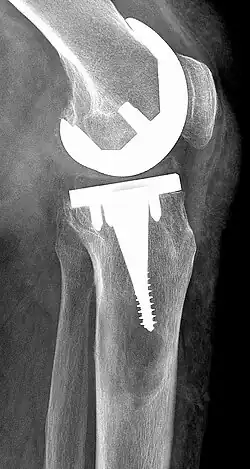

- Auch der Abrieb von Prothesen, wie beispielsweise bei einer Gelenkprothese, kann zu Fremdkörperreaktionen führen. Insbesondere die Gelenkpfanne – meist aus Polyethylen gefertigt – neigt zu Abrieb, der die Synovia reizt und so zu einer Synovitis prothetica führen kann. Innerhalb von zehn Jahren führt dies bei 25 Prozent der Gelenkprothesen zu einer Lockerung der Gelenkpfanne.[1]